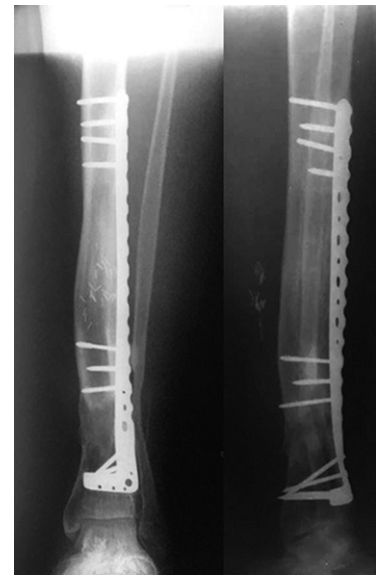

等确定感染控制了,软组织条件好了,行II期手术,本文作者介绍了一种组合式固定方式+骨搬运。

➤ 1、骨科外固定支架单边(用于骨搬运+支撑);

➤ 2、锁定长钢板(维持长度+支撑);

➤ 3、I期术后12个月,搬运到位后,直接上螺钉固定,去除外固定架。

I期术后2年,患者终于获得骨愈合。